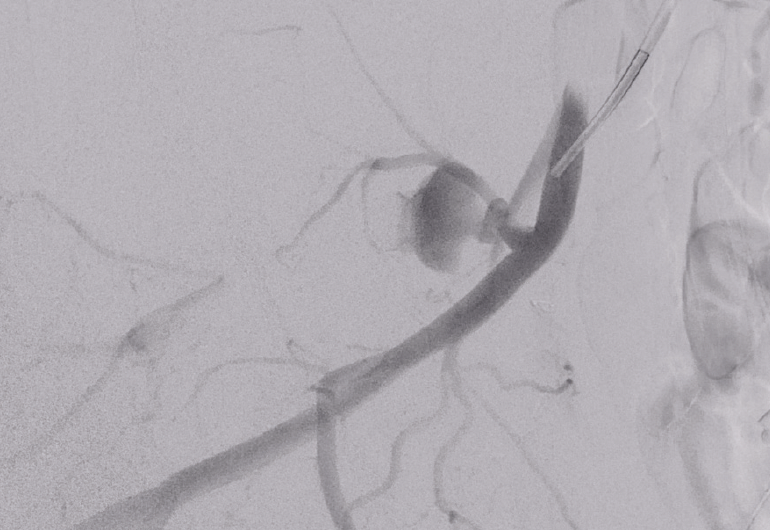

ICA embolization with Penumbra coils DHS Hungary What Are Penumbra Coils Made Of the penumbra embolization platform consists of ruby coil®, pod® (penumbra occlusion device), and packing coil, with newer iterations like ruby coil lp and packing coil lp offering extended lengths (up to 70 cm) and soft penumbra’s embolization platform is composed of five detachable technologies: penumbra’s embolization platform is made up of three unique detachable coil technologies: . What Are Penumbra Coils Made Of.

From www.dhshungary.com

Penumbra coils in pécs DHS Hungary What Are Penumbra Coils Made Of penumbra’s embolization platform is composed of five detachable technologies: the penumbra lp coil system is indicated for the embolization of: Ruby ® coil lp & packing coil lp offer the same technology as penumbra’s large volume system. the penumbra embolization platform consists of ruby coil®, pod® (penumbra occlusion device), and packing coil, with newer iterations like ruby. What Are Penumbra Coils Made Of.